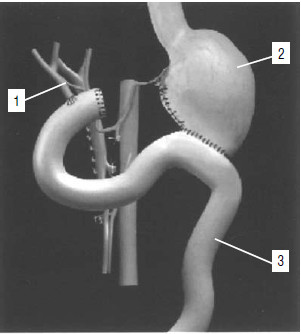

Рис. 111. Холецистоеюноанастомоз с межкишечным анастомозом по Брауну. 1 – опухоль головки ПЖ, 2 – желчный пузырь, 3 – тощая кишка, 4 – межкишечный анастомоз по Брауну, 5 – холецистоеюноанастомоз.

Паллиативные операции составляют до 80 % всех вмешательств, которые выполняют при РПЖ, так как опухоль рано метастазирует и распространяется на близлежащие органы. Они преследуют следующие цели: 1) устранить холестаз и желчную гипертензию, 2) ликвидировать непроходимость желудка или ДПК при наличии таковой, 3) уменьшить болевой синдром. Для устранения механической желтухи применяются различные виды билиодигестивных анастомозов или наружное дренирование желчных путей с реинфузией желчи. Соустье желчного пузыря с тонкой кишкой (операция Монастырского) выполняется при проходимом пузырном протоке. Операция технически несложна и малотравматична, но существенным ее недостатком является опасность развития рецидива желтухи при прорастании опухолью пузырного протока (рис. 111).

Гепатикоэнтероанастомоз производится в случаях, когда опухолевый инфильтрат распространяется по желчному протоку в направлении ворот печени, захватывая пузырный проток и оставляя свободным общий печеночный проток, или только долевые протоки печени. При распространении опухоли в ворота печени иногда накладывают анастомозы с внутрипеченочными желчными протоками (рис. 112).

Рис. 112. Схема операции наложения обходного гепатикоеюноанастомоза при раке головки ПЖ, осложненном механической желтухой. Анастомоз сформирован на дренаже, выведенном через анастомозированную кишку. 1 – общий желчный проток, 2 – тощая кишка, 3 – дренаж, 4 – поджелудочная железа, 5 – опухоль головки ПЖ